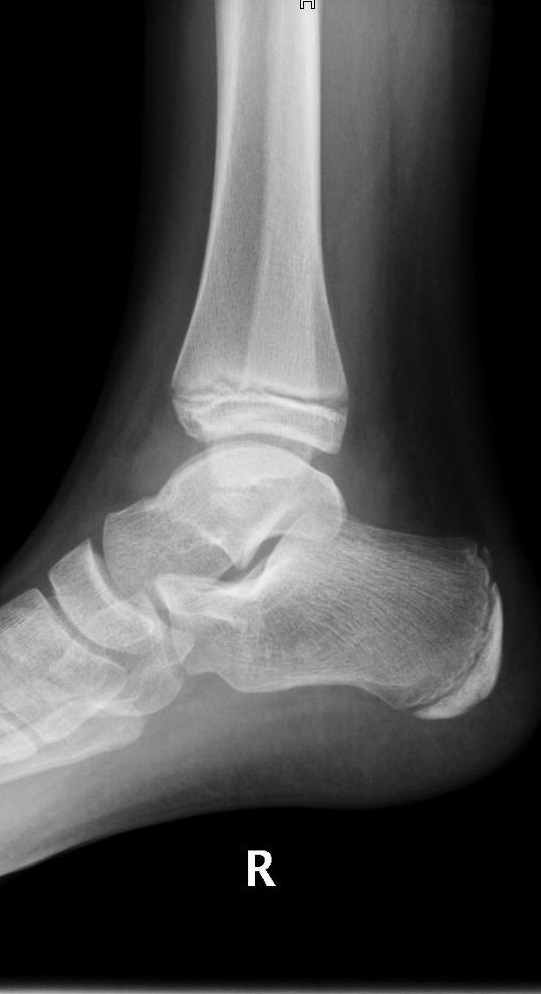

Niña de 11 años de edad sin antecedentes de interés que acude a Urgencias por dolor a nivel del maléolo externo del miembro inferior derecho tras un movimiento anómalo del pie con inversión del tobillo hace 2 días. Asocia tumefacción e impotencia funcional leves. Le han administrado analgesia en el domicilio sin mejoría. A la exploración, presenta tumefacción y dolor selectivo a la palpación del maléolo externo y los ligamentos peroneoastragalinos anterior y posterior. No crepitación ni resaltes óseos ni hematoma. No presenta limitación de la movilidad pasiva y si presenta limitación a la movilización activa por dolor. Se realiza radiografía anteroposterior (Figura 1) y lateral (Figura 2) del tobillo derecho.

Figura 2. Proyección lateral.